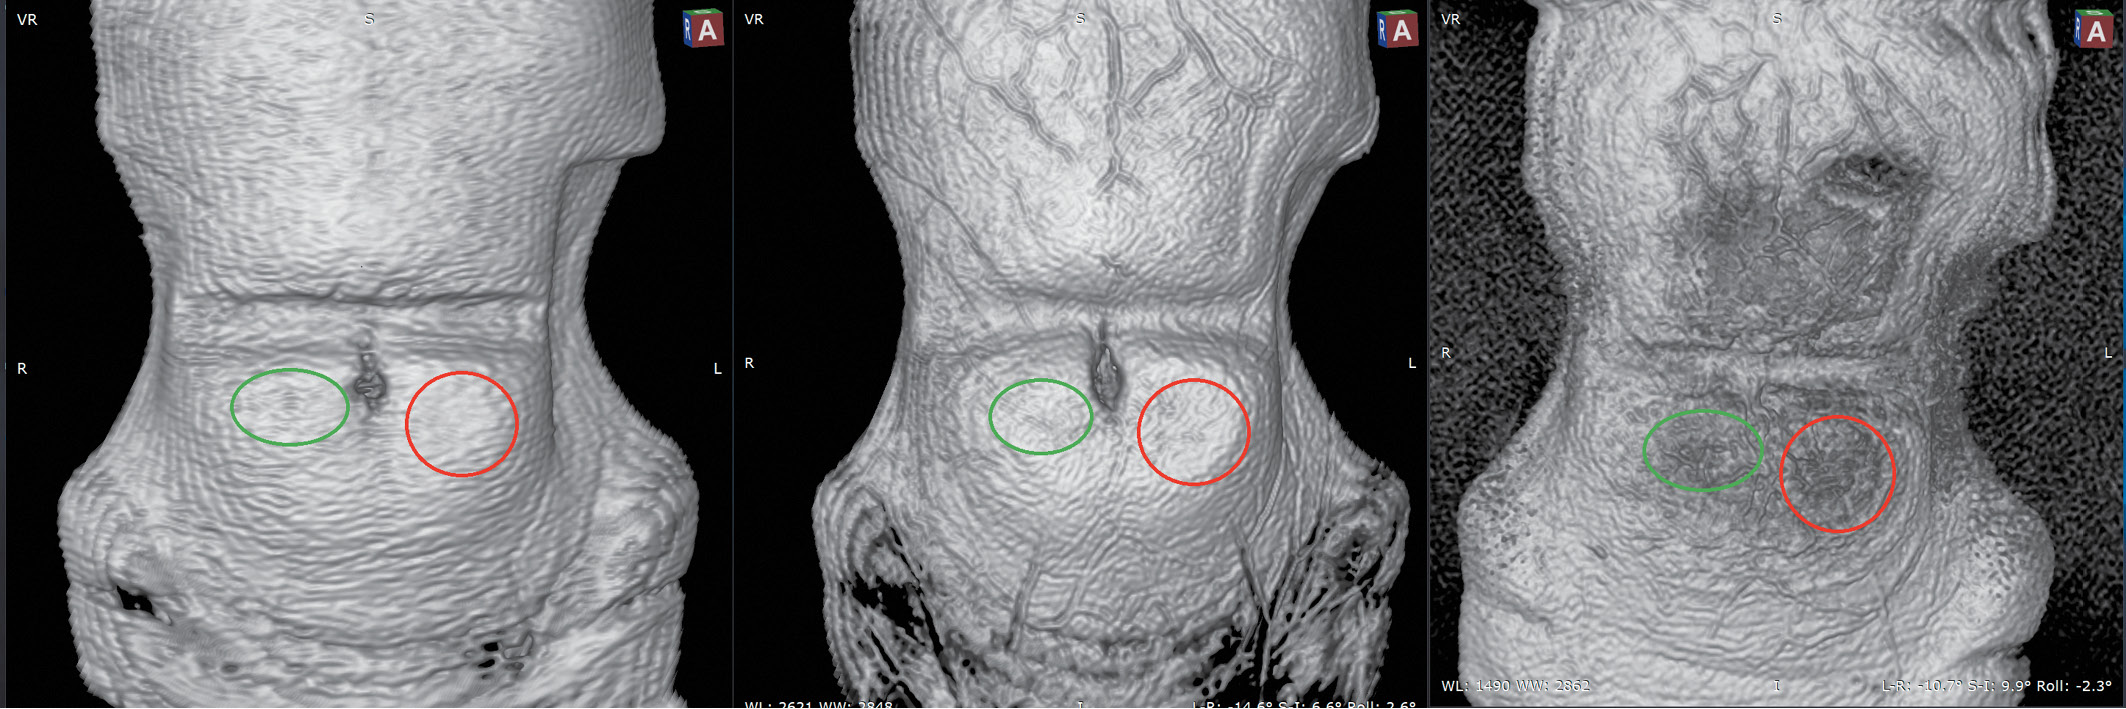

7. Fig. 7. 3D reconstruction of MRI images of areas of lipohypertrophy in the subcutaneous tissue of the anterior abdominal wall in the area of insulin injection in a patient with diabetes mellitus: MR tomograph General Electric Discovery MR750W (magnetic field 3.0 T). Coil: Body 48 AA, reconstructed diameter 400 mm, matrix 320x320. Technology (from left to right): T1-WI (TR 195.0; TE 2.1; cut 3 mm); T2-WI Propeller (TR 4000.04 ms; TE 95.8 ms, 3 mm cut), T2-WI FS Rtr Propeller (selective grease suppression; TR 4000.04 ms; TE 95.76 ms, 3 mm cut). In all cases - synchronized coronal projection (slice thickness - 3 mm). Images were obtained in 3D-Volume Rendering mode (multi-planar surface reconstruction; Skin B / W was used in all cases) in the RadiAnt DICOM Viewer Ver program. 5.0.1.21910 (64-bit) [51]. On T1-WI, a green oval shows the zone of lipohypertrophy to the right of the umbilical ring; when comparing T2-WI and T2-WI FS, it is seen that the suppression of the lipid component is negligible (compared to the contralateral side). On T1-WI, the red circle shows the area of lipohypertrophy of adipose tissue to the left of the umbilical ring (mirror image). When comparing T2-WI and T2-WI FS, it is seen that the suppression of the lipid component is significant (compared to the contralateral side). Here and in fig. 8, 9: B-ya Ya., 25 years old, type 1 diabetes mellitus for 20 years, therapy with insulin analogues (glargin 100 U / ml and lizpro). | |

(328KB)